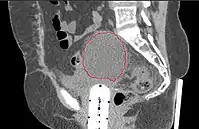

- CT of abdomen/pelvis typically not necessary, unless suspicion of extra-pelvic disease

- MRI is best modality for assessing myometrial invasion and cervical involvement, but provides no additional information if surgery is planned anyway

- Symptomatic lymphoceles are typically managed initially with percutaneous CT-guided drainage, surgical therapy may be required

- Postoperative Lymphocele